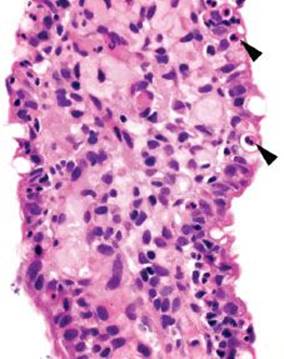

Figure 3.51 Acute ileitis pattern. Acute ileitis refers to acute inflammation in the epithelium of the ileum (arrowheads). It is most commonly caused by medication, infection, and inflammatory bowel disease.

Similar to that in the acute duodenitis pattern, acute inflammation in the epithelium of the ileum can qualitatively be scored “mild,” “moderate,” or “marked” based on the relative prominence of acute inflammation in the epithelium (Figs. 3.51–3.55). Comparatively, the acute ileitis pattern is associated with a slightly modified differential diagnostic list of etiologic considerations. In this section, the discussion emphasizes etiologic considerations particularly important to the ileum.